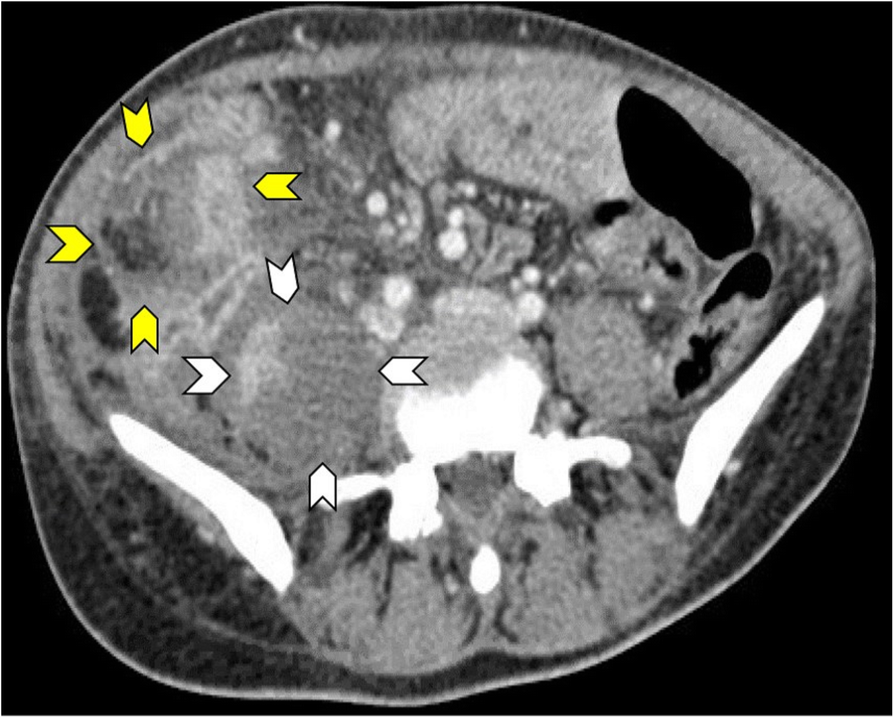

Fig. 3

A 31-year-old woman presented with right iliac fossa and right-sided back pain for 1-month duration. She was afebrile, had no cough or night sweats but was anemic. Abdominal CT scan with intravenous contrast showed an inflammatory mass in the right iliac fossa (yellow arrow heads) with sinus tracts communicating to a right iliopsoas abscess (white arrow heads). The patient was from an endemic area of tuberculosis and was treated with anti-tuberculous drugs